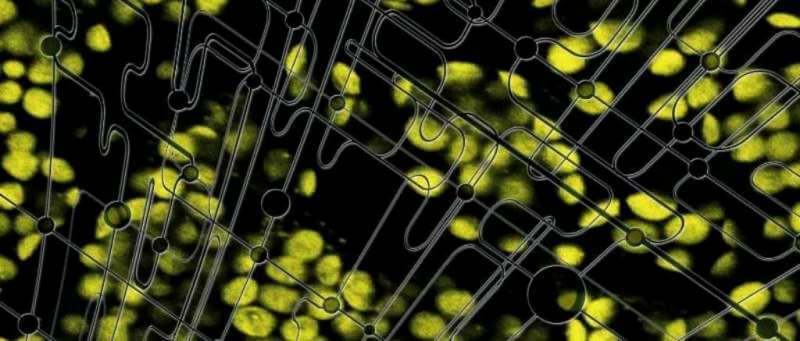

Aunque una misma enfermedad puede presentar perfiles muy diferentes de un paciente a otro, a menudo en medicina se prescribe todavía la misma terapia para todo el mundo. Hasta ahora los investigadores han usado técnicas y modelos animales de investigación genéricos, pero la medicina personalizada impulsa un cambio de paradigma para diseñar tratamientos hechos a medida para cada persona y mucho más dirigidos a su enfermedad: la medicina de precisión, un campo donde convergen las ciencies computacionales, la nanotecnología y las ciencies de la vida. Estas tecnologías mejorarán significativamente los cultivos in vitro actuales –lque reflejan pobremente la fisiología del paciente– y permitirán crear plataformas para simular el comportamiento del cuerpo humano in vivo.